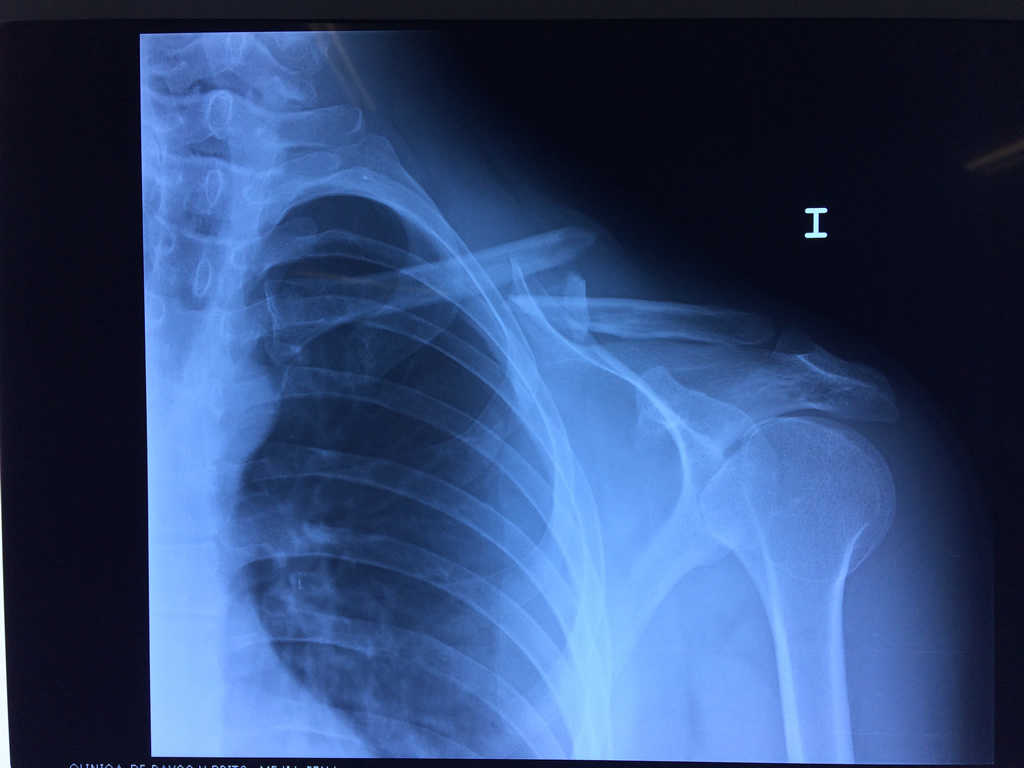

Cirugías de Calcaneo - Clavícula

La clavícula es un hueso largo, con forma de "S" itálica, situado en la parte anterosuperior del tórax. Junto con la escápula forman la cintura escapular. Se puede palpar por toda su longitud y se extiende del esternón al acromion de la escápula, siguiendo una dirección oblicua lateral y posterior.